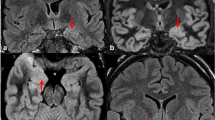

When comparing the prevalence of the findings before and after surgery in the 17 patients who underwent surgery, the frequency of limbic system atrophy tended to be higher after surgery than before surgery (Table 3). Limbic system atrophy ipsilateral to the epileptic focus was found in the following structures after the surgery: 5 (29.4%) in the fornix (Fig. 1); 9 (52.9%) in the mamillary body; 2 (11.8%) in the MTT (Fig. 2); and 2 (11.8%) in the thalamus. The frequency of mamillary body atrophy was significantly higher after surgery than before surgery (p=0.015), but there was no significant difference for the other structures.

Atrophy of the ipsilateral fornix, mamillary body, and thalamus. a Axial and b coronal T2-weighted MR images obtained 2 months after selective amygdalo-hippocampectomy reveal that the ipsilateral fornix is smaller than that on the other side (arrow). c Axial T1-weighted MR image reveals asymmetry of the mamillary body. The left mamillary body is smaller than the right side (arrow). d Axial T2-weighted MR image reveals the atrophy of the left thalamus. A subtle hyperintense area is also identified in the left thalamus (arrows)